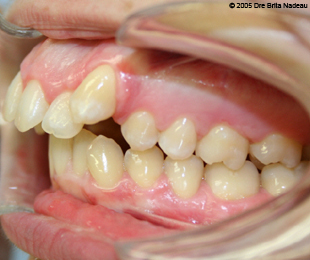

Marie-Hélène Cyr - Left lateral intraoral view - Before orthodontic treatments and orthognathic surgeries (November 24, 2005)

November 24, 2005 - The extrusion of my premaxilla is very flagrant on this left lateral view.